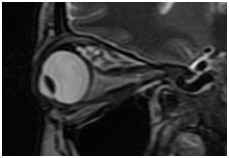

眼眶(病例-眼上静脉扩张)